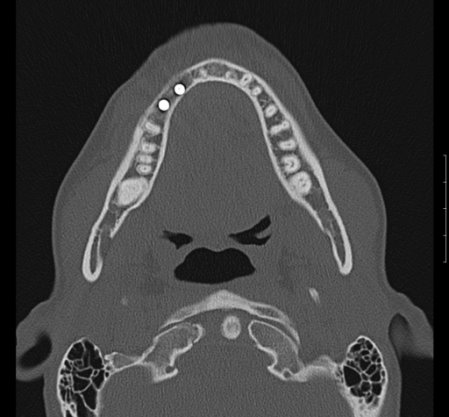

Zur genauen Planung der Kieferkorrektur wurde ich zum CT geschickt. Aus den scheibchenweisen Bildern setzte der Computer ein dreidimensionales Bild zusammen. Dabei ist auch sehr deutlich dieses verlagerte Knochenstück zu sehen.

Zwischenzeitlich stand auch mal die Überlegung im Raum, eine Kinnplastik durchzuführen, bei der die Kinnspitze abgesägt und danach im "richtigen" Winkel wieder aufgesetzt wird. Das klang natürlich auch erst mal ein bissel erschreckend - aber schließlich zählt das Ergebnis. Nach Auswertung der 3-D-Annimation wurde dann allerdings "nur" die erstbeschriebene Kieferkorrektur durchgeführt.